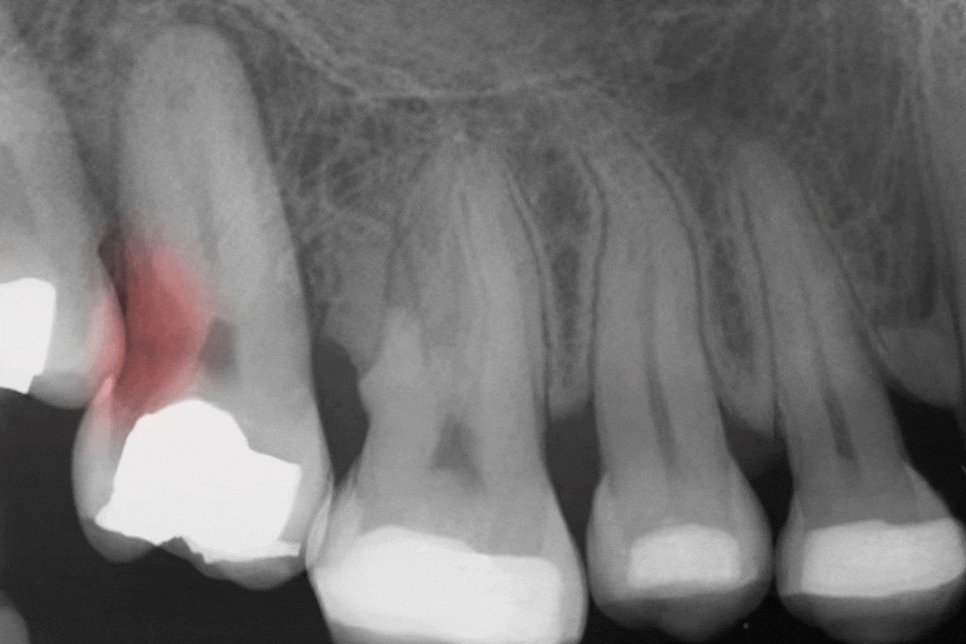

제일 대표적인 원인은 미세누출로

레진의 경우에는 재료 특성상

중합 수축이 발생해

레진이 굳는 과정에서 미세하게 수축하면서

변연 부위에 응력이 생기고

이로써 접착력이 약해질 수 있습니다.

또한 반복되는 저작력과 온도 변화도

수복물에 변화를 일으킬 수 있습니다.

크라운의 경우에는 잇몸이 내려가면서

경계 부위가 드러나게 되고

그 틈으로 세균이 침투하기 쉬운 환경이 됩니다.

또한 접착제가 오랜 기간에 걸쳐 서서히 약해진다면

변연 적합도가 떨어질 수 있습니다.